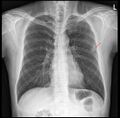

1. X-RAY 촬영. 전면 및 측면 두 장

1. 오늘 찍은 X-RAY보면서 괜찮다. 폐렴 없다.